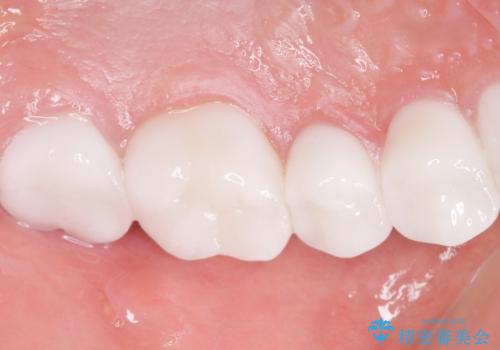

虫歯をしっかりと治療したのち、オールセラミッククラウンによる補綴治療を行いました。

憧れのヴィジュアル系バンドマンのような白い歯になり、喜んで下さいました。

不適なレジン充填によるデコボコがなくなったことで歯磨きしやすくなり、また気にされていた咬み合わせも良くなり、ご満足頂けました。

クラウンの種類:オールセラミッククラウン スタンダード

シェード:NW0